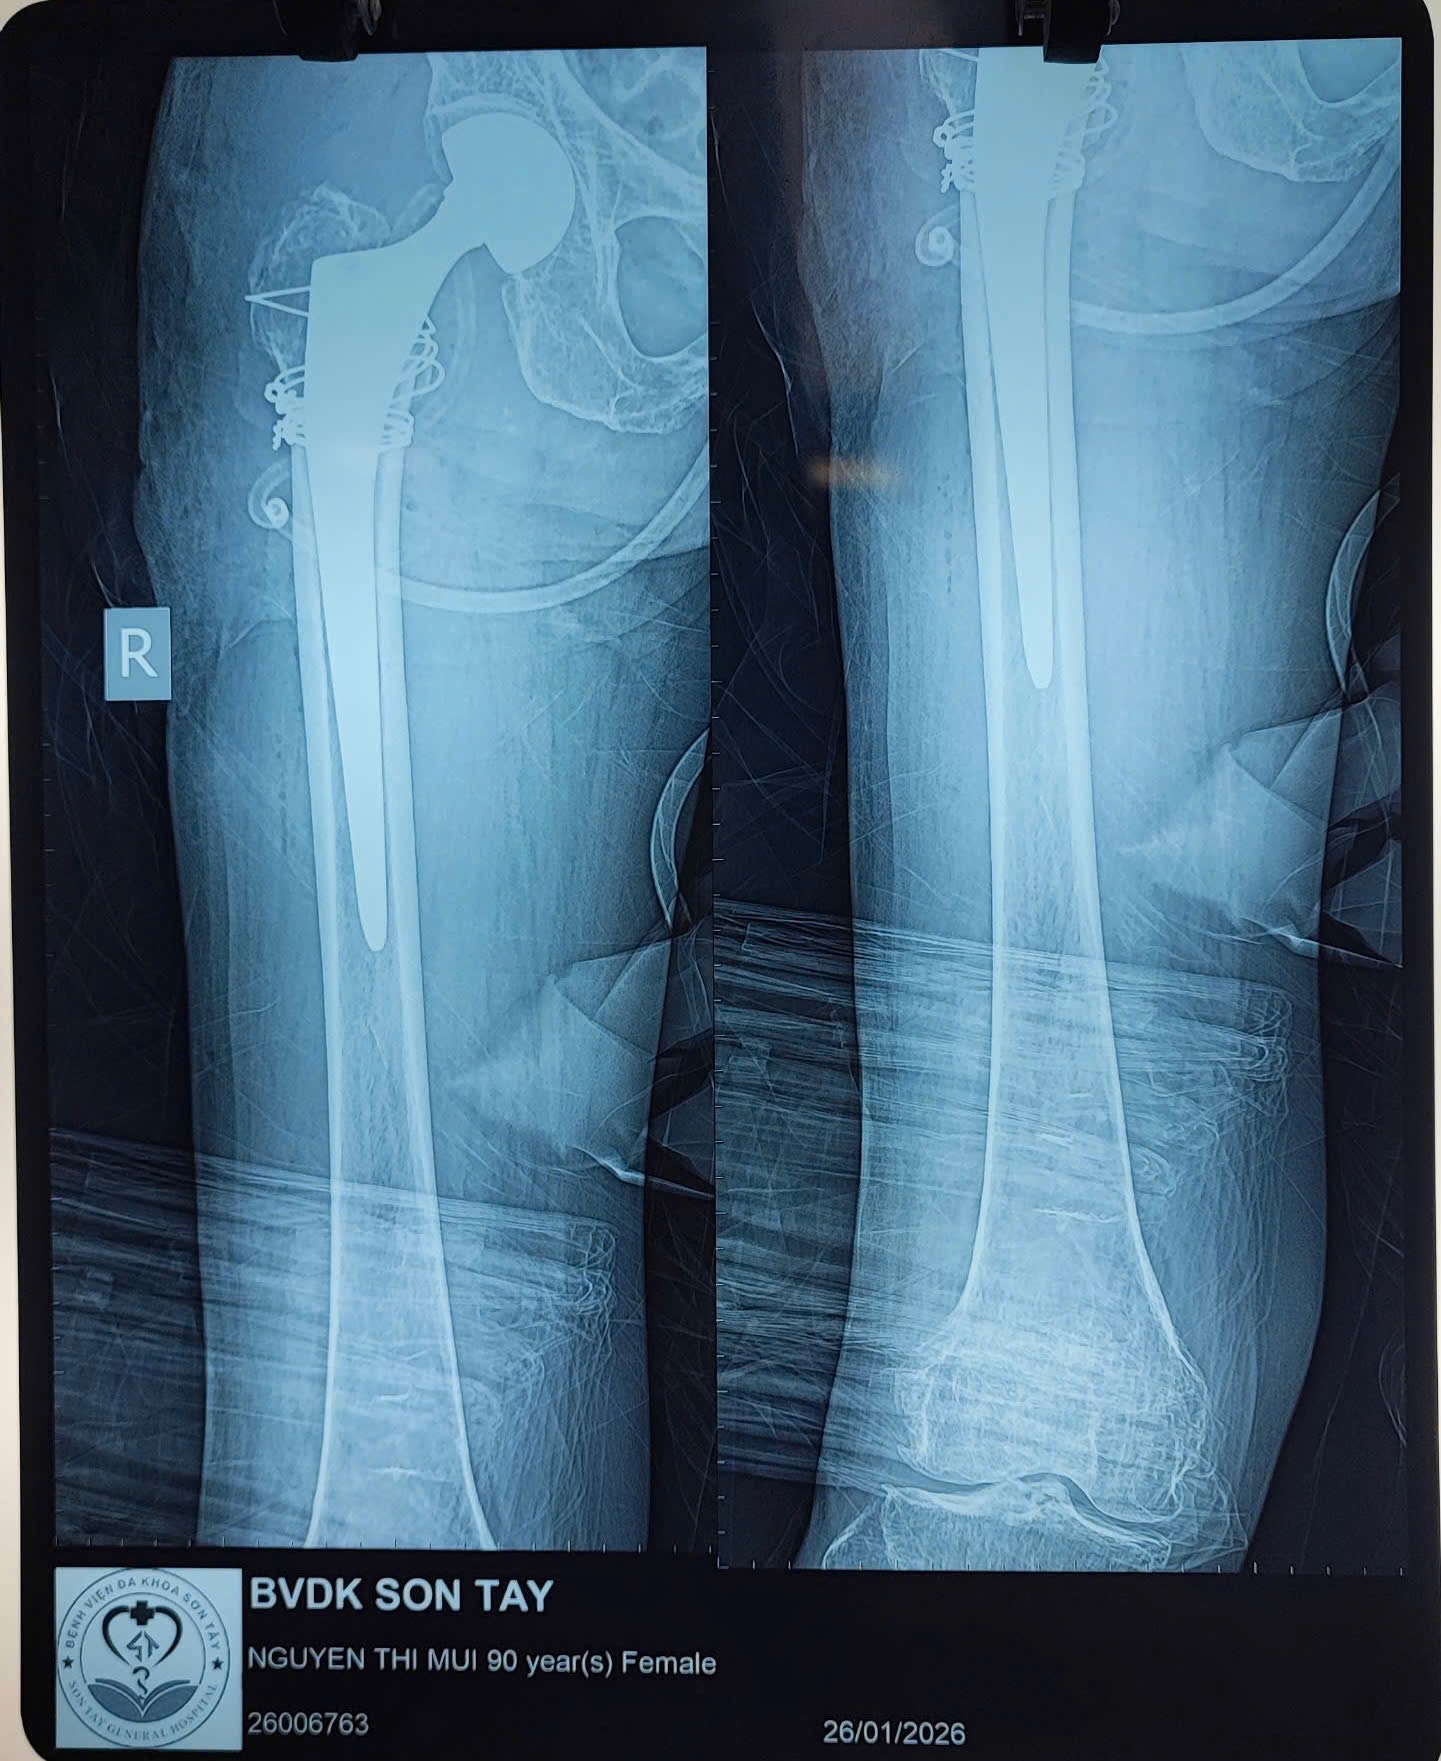

📅 Ngày 26/01/2026, Khoa Ngoại Chấn thương – Bệnh viện Đa khoa Sơn Tây đã phẫu thuật thành công thay khớp háng bán phần cho bệnh nhân Nguyễn Thị M. (90 tuổi ở Yên Thành, Suối Hai, Hà Nội)

📸 Kết quả X-quang và CT cho thấy tổn thương phức tạp đầu trên xương đùi, nguy cơ cao nếu điều trị bằng phương pháp kết hợp xương thông thường. Sau hội chẩn liên chuyên khoa (Ngoại Chấn thương, Gây mê hồi sức, Nội tim mạch), ê-kíp điều trị thống nhất chỉ định thay khớp háng bán phần nhằm giúp bệnh nhân giảm đau nhanh, vận động sớm, hạn chế biến chứng do nằm lâu.

👨⚕️ Ca phẫu thuật được thực hiện an toàn, ít xâm lấn, thời gian mổ ngắn, kiểm soát huyết động tốt. Sau mổ, bệnh nhân tỉnh táo, các chỉ số sinh tồn ổn định, được hướng dẫn tập vận động sớm, góp phần giảm nguy cơ viêm phổi, loét tỳ đè và thuyên tắc mạch.